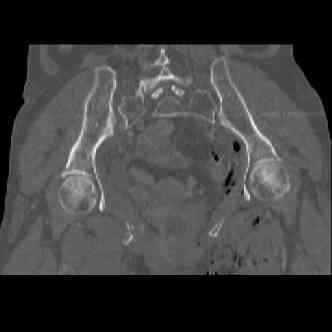

attached are several CT cuts. please let me know if you need more. the CT is pre-pelvic ex-fix placement.

I wouldn't plate the front.

But I would add screws posteriorly.